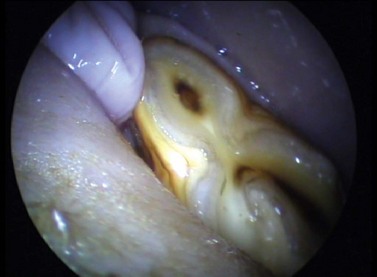

Abrasions or lacerations of the cheeks within the oral cavity can arise from direct trauma to the soft tissues by sharp or prominent buccal enamel points/edges or displaced or fractured teeth. Injuries may be detected, when acute, as mucosal lacerations or fresh abrasions (Fig. 9.1) or when chronic (characterized by ulceration with thickened mucosal edges or scar tissue; Fig. 9.2). The removal of the inciting cause usually resolves the problem.

Fig. 9.1 A small fresh buccal ulcer adjacent to a maxillary cheek tooth.